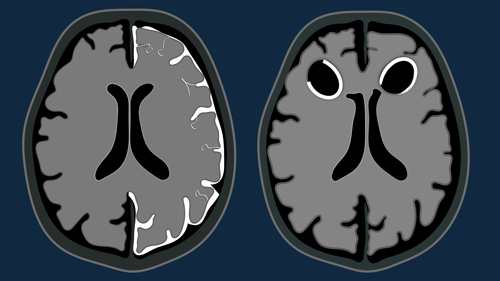

Multiple Sclerosis 2.0